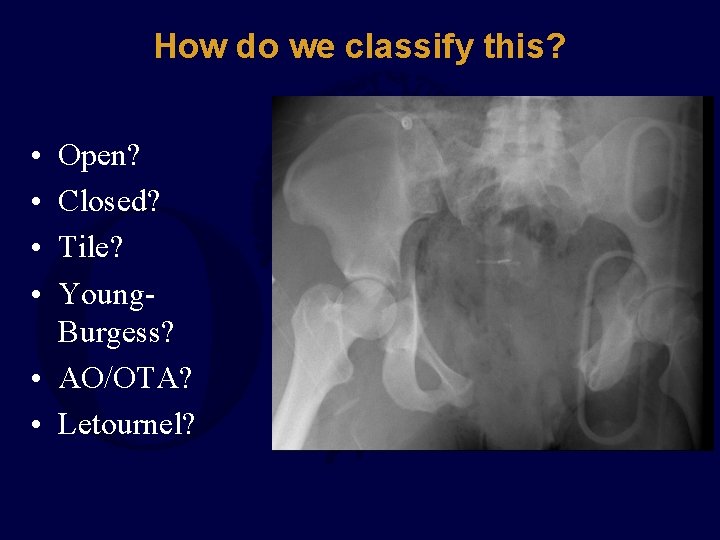

How do we classify this? • • Open? Closed? Tile? Young. Burgess? • AO/OTA? • Letournel?